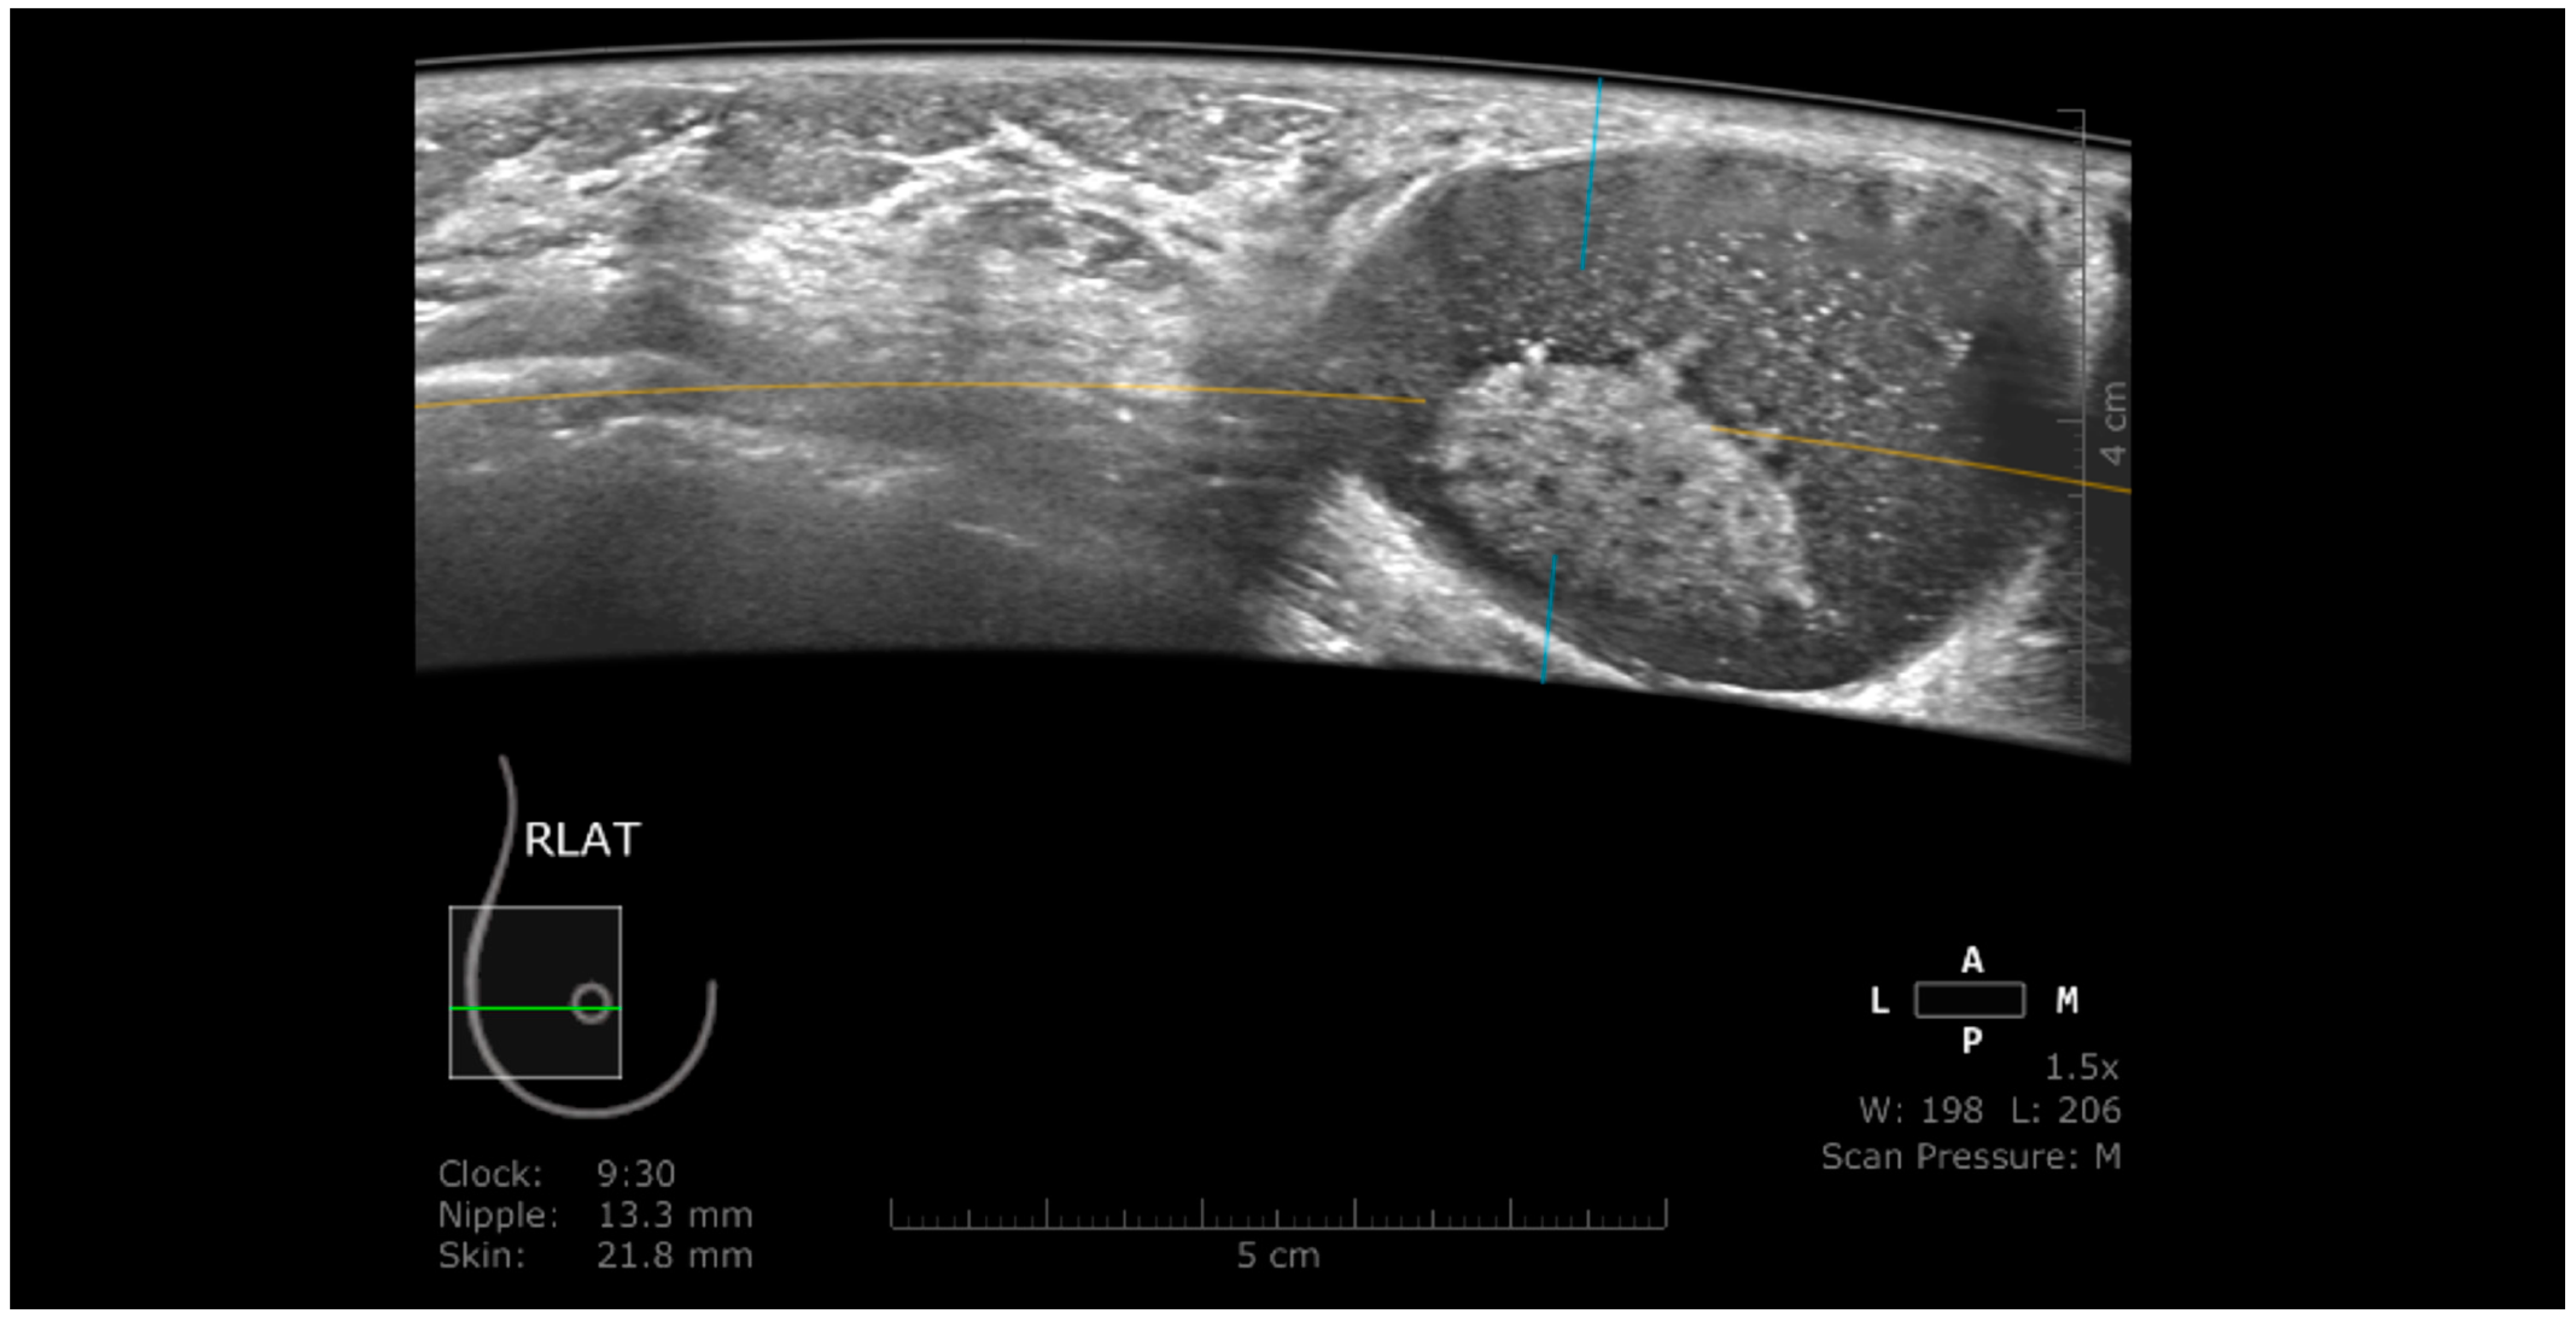

3.1. Technique and Artifacts

3.1.1. Limitations Related to the Technique

3.1.2. Artifacts

Artifacts Induced by the Use of Ultrasound Gel

Air Interposition

Insufficient Compression

Probe Motion Artifacts

Breathing Artifacts

Skip Artifact

Nipple Artifact

Attenuation Areas

White Wall Sign